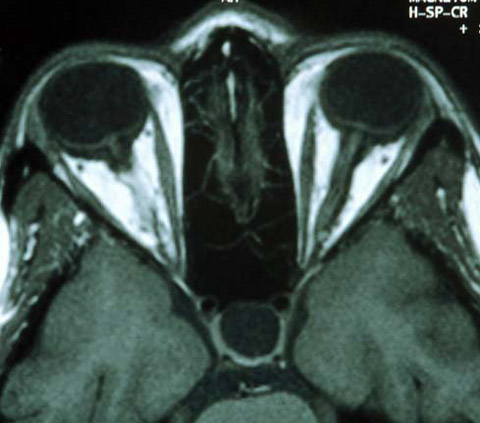

20 year old woman with back pain, neck pain, and blurry vision OS

The patient is a 20-year-old woman seen at the Massachusetts General Hospital for symptoms of back pain, neck pain, and blurry vision in the left eye for 10 days. The patient describes the blurry vision as being constant.